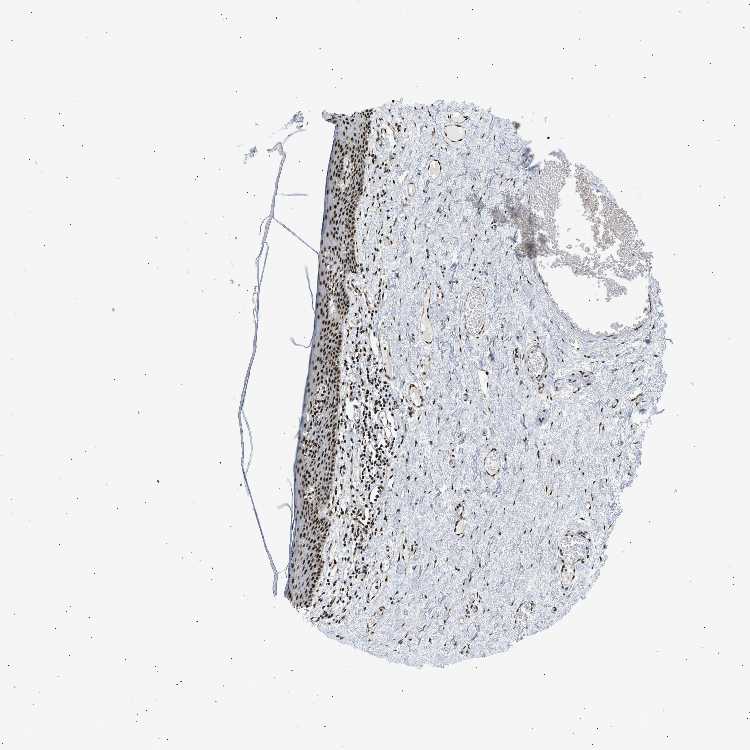

SKIN 2 - Antibody stainingi

Antibody staining in the annotated cell types in the current human tissue is reported as not detected, low, medium, or high, based on conventional immunohistochemistry profiling in selected tissues. This score is based on the combination of the staining intensity and fraction of stained cells.

Each image is clickable and will lead to virtual microscopy that enables deeper exploration of all samples and also displays staining intensity scores, fraction scores and subcellular localization as well as patient and tissue information for each sample.

Antibody HPA062997Antibody CAB014874

Epidermal cells HighHigh